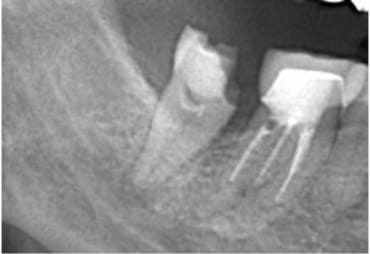

近所のかかりつけの歯科医院で、「再治療できないから奥歯を抜くしかない」と言われた。

あきらめきれず、HPで探して当院へ来院。

外すと中がドロドロに虫歯に感染していました。

折れて残っていた機具を除去

根管の中を洗浄し、無菌に近い空の状態にした。

根管の中を封鎖し終了。

治療後病気がなくなり骨が再生した